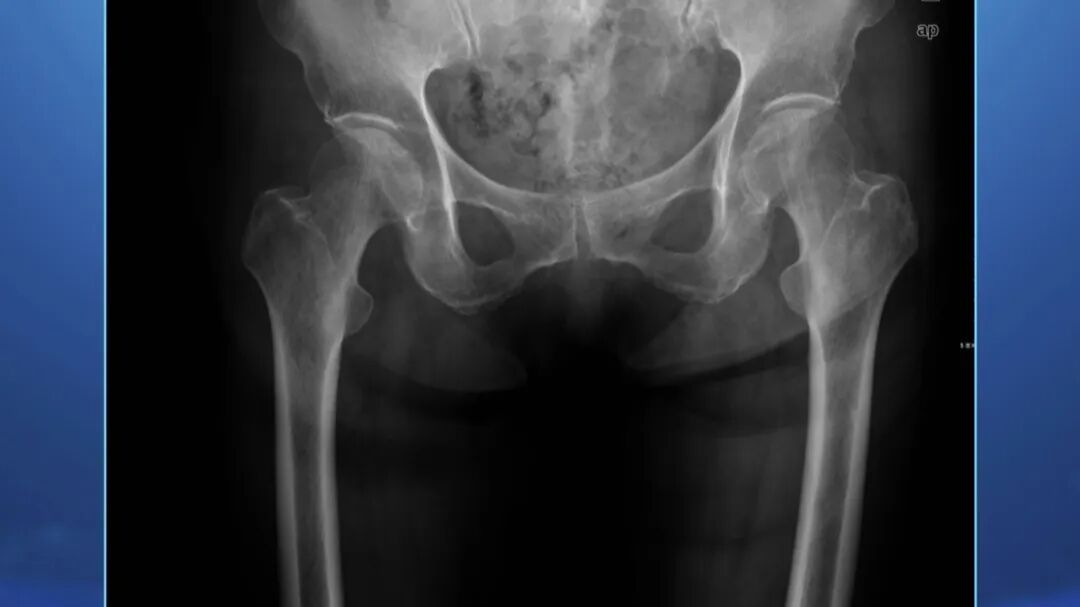

髋部由髋臼、股骨头、股骨颈、大粗隆等结构组成,股骨头连接的股骨颈和粗隆部位,十分容易发生嵌插性骨折。

由于老年人常会伴有骨质疏松,摔倒后,髋部的股骨颈部位容易断裂,两个断碴如果挤到一起,就被称为嵌插。

因此老年人摔倒后,骨头断裂部位暂时处于一个插住的状态,虽然有疼痛的感觉,但仍然能够支撑完成一些基础的活动,会导致病情被耽误。

髋部的嵌插性骨折属于隐形骨折,早期在医院就诊时很容易漏诊,导致耽误病情,一般医院会建议患者观察三周以上。这种骨折发生以后,对老年人的日常生活影响非常大。

一型:断裂部位挤到一起,通过片子看不到中间断裂处,被称为不完全骨折。

二型:和一型部位类似,但是通过片子能够看到中间的断裂线,且断裂处没有错位、分开。

三型:完全错位,一型、二型骨折在运动后,很容易变成三型。

四型:最为严重,不仅错位而且断裂的两个部分发生相对旋转,预后最差。

一型、二型的早期治疗效果好,三型、四型的治疗效果差。